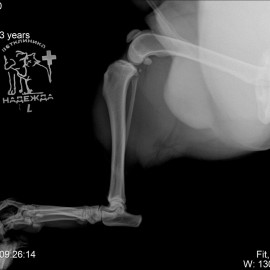

Пациент собака по кличке Рич.

После проведённых исследований был поставлен диагноз: пателлярный вывих левого коленного сустава, разрыв передней крестообразной связки левого коленного сустава.